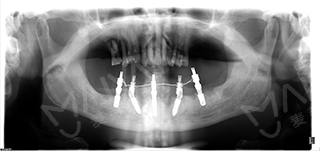

种植5颗牙后口腔全景片

经过前期的牙周清洁、治疗后,根据李老口内实际情况,为达到更好的增加负重、增强咀嚼能力效果,麦芽口腔种植医师团队对ALL-ON-4种植技术进行升级和改造,为其量身定制了“ALL-ON-5”种植方案,治疗后总共恢复24颗牙齿。